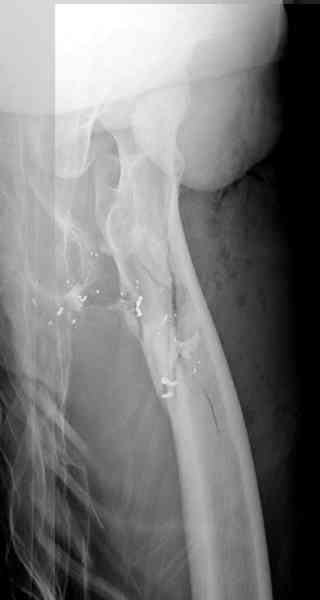

В нашем случае 21 летний боец уличного фронта, фиксацию провели на следующий день, зафиксирован интрамедуллярным штифтом. Не стали делать первичную хирургическую обработку точечной раны, зафиксирован как есть. Клинические снимки:

Конечно, наш случай не эталон, возможно, на месте вам виднее, может быть, нет необходимости ориентироваться на зарубежные ссылки, если получается лечить аппаратом Илизарова на месте, почему нет? Необходимо посмотреть собственный арсенал, чем фиксировать, и какая теория, иначе любой отличный метод можно превратить в источник остеомиелита.